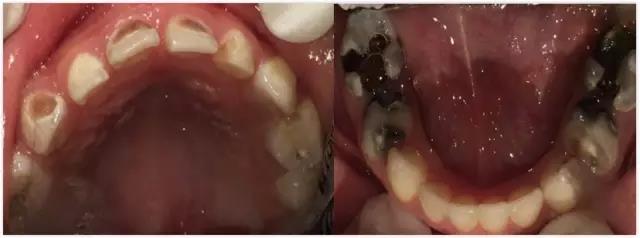

先来说说蛀牙是什么?北京儿童医院口腔科副主任医师高艳霞介绍,从时间角度讲,蛀牙是一个慢性病。蛀牙是指牙齿从浅到深一系列的改变,从最开始的白垩色,通俗的说就是发现孩子的牙齿不那么透亮,到雾状变化,再到开始变软,有黑色、褐色的变化,出现掉渣的情况,直到发展成明显的蛀牙。

图/北京儿童医院口腔科

在从浅到深的变化中,牙齿始终处在一个动态平衡阶段,受两种因素影响,一种是破坏性因素、保护性因素,破坏性因素会造成牙齿表面变软、矿物质缺失,但同时也有保护性因素促进矿物质再次沉积。如果动态平衡被打破,就会发生蛀牙。